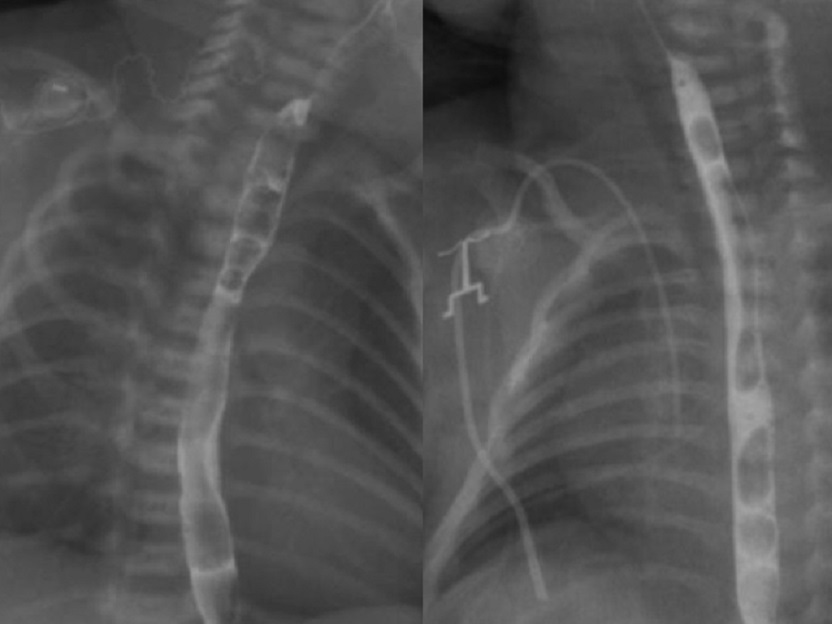

Figure 4

Case 2: Babygram showing gas in the bowel loops and a lateral position of the Replogle tube (arrow). Cervical subcutaneous emphysema is visible (*). Hyperlucency of the upper pouch is not clearly distinguishable.

Figure 5

Case 2: A poor quality intra-operative esophagram showing a tiny upper pouch (arrow) without any leaks

Figure 6

Post-operative esophagram of both cases showing the absence of leaks or strictures.